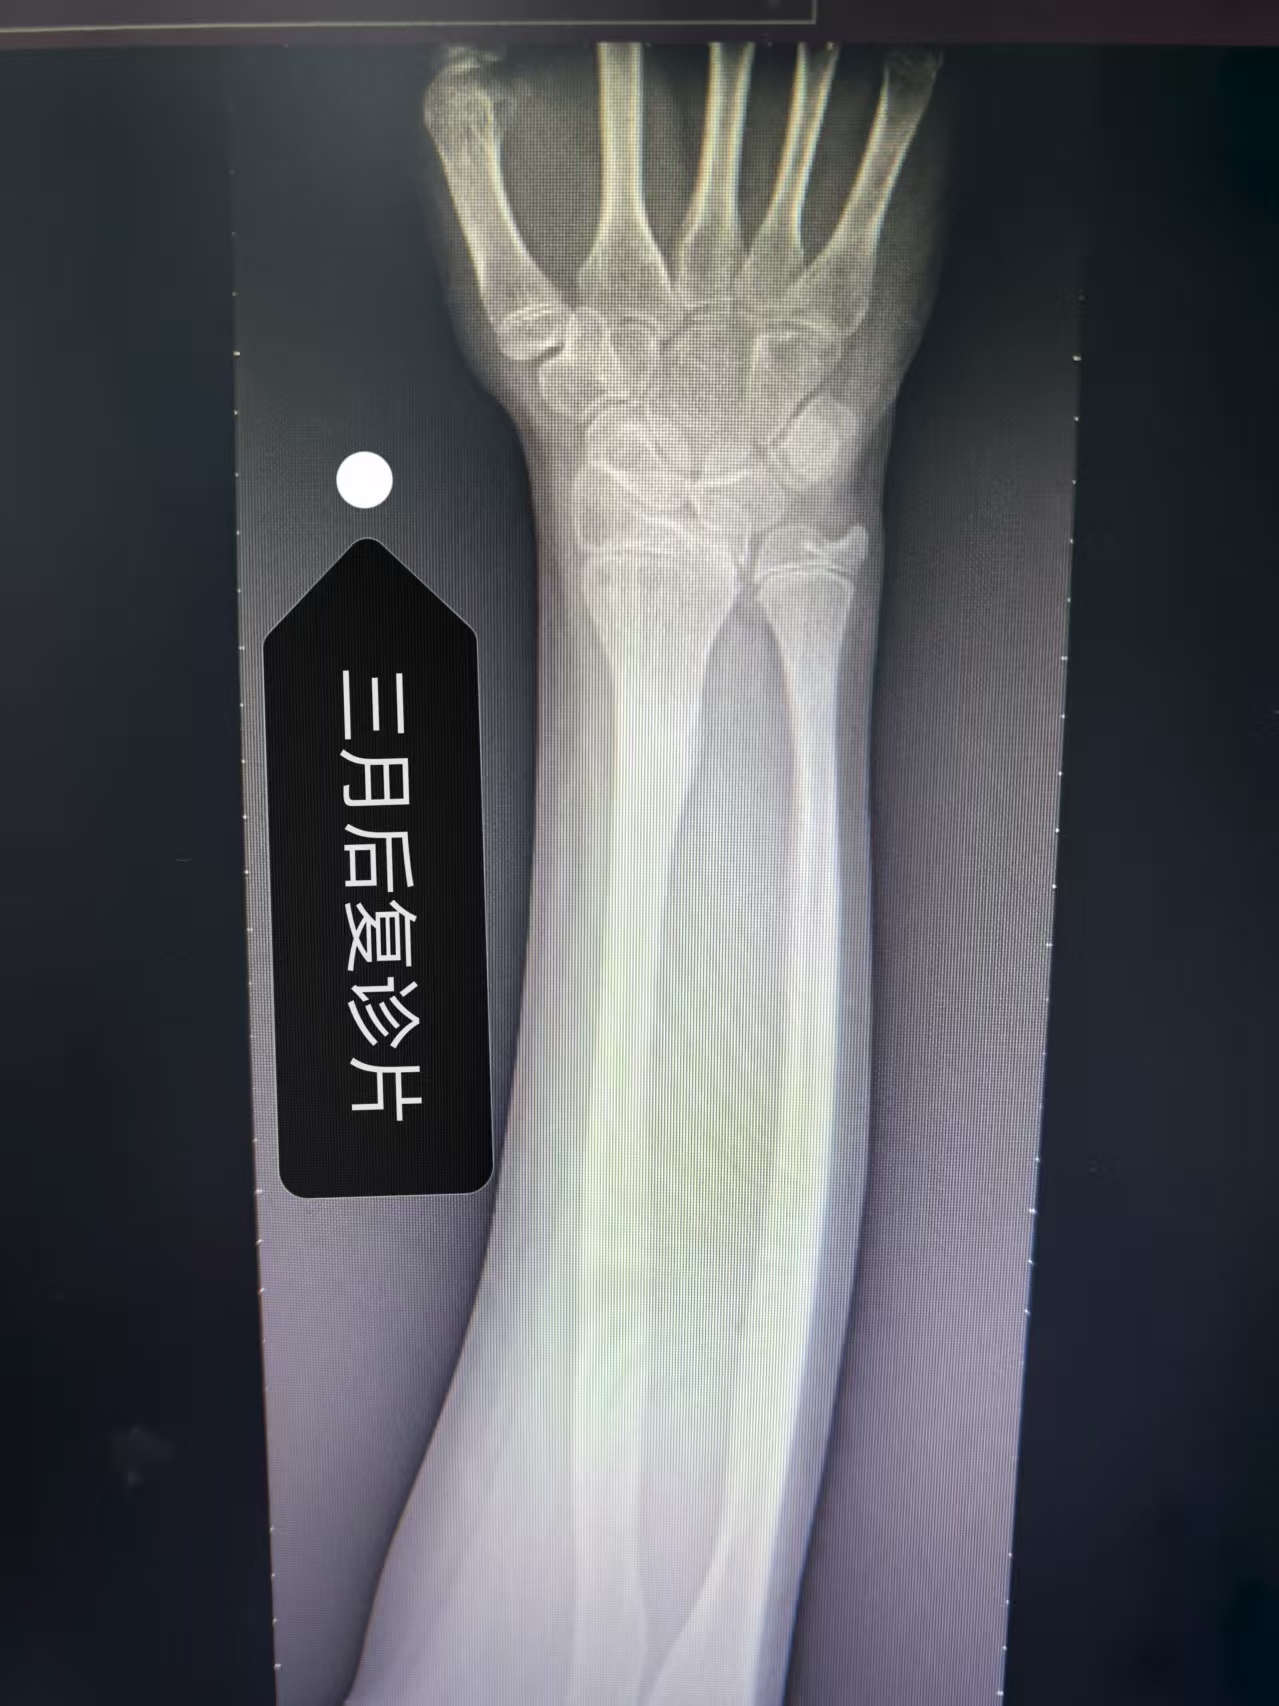

(这二张DR片,是经我院骨科运用传统中医手法复位加夹板外固定后即刻照片,疗效满意)